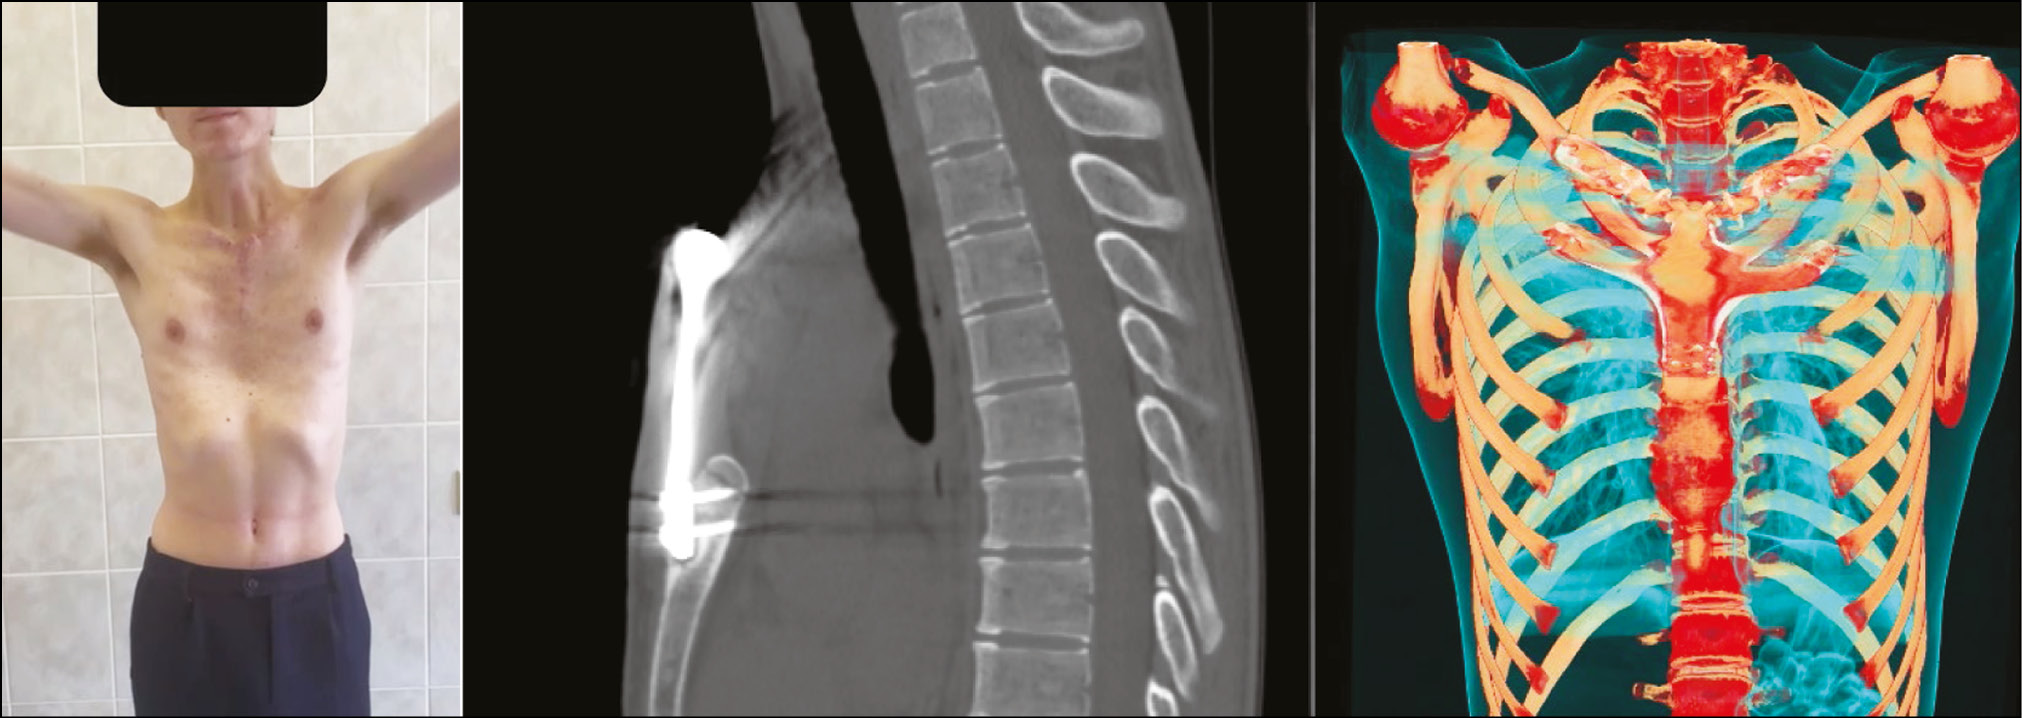

При помощи кортикальных винтов и серкляжных нитей произведена фиксация импланта к костным структурам. При функциональном тесте отмечены жёсткая и стабильная фиксация нижнего полюса импланта и сохранение движений в грудино-ключичном сочленении при функциональных пробах. Имплант поэтапно закрыт грудными мышцами. Грудино-ключично- сосцевидные мышцы подшиты к импланту и мягким тканям грудных мышц, прилегающих к импланту. Объём кровопотери составил 240 мл, время хирургического вмешательства — 3 ч 35 мин. Нахождение в условиях реанимационно-анестезиологического отделения — 1 сут, далее пациент был переведён в стационар. Дыхательные расстройства в послеоперационный период не зарегистрированы. Отмечена гематома в объёме 40 мл в проекции грудной мышцы справа, на фоне двукратной пункции гематома полностью эвакуирована. По данным КТ-контроля положение импланта стабильное (рис. 8).

Рис. 8. Рентгенологическое исследование, КТ-реконструкция и внешний вид пациента Г. после хирургического вмешательства.

Динамика и исходы

Пациент активизирован на 5-е сут в кольцах Дельбе для стабилизации плечевого пояса. На 14-е сут выписан на амбулаторное наблюдение по месту жительства. Корректор осанки грудного отдела позвоночника назначен на 3-й мес после оперативного вмешательства. Разработка движений в верхнем плечевом поясе под контролем реабилитолога — через 2 мес с момента операции. По контрольным снимкам через 12 мес признаков рецидива и нестабильности в импланте не обнаружено. Отмечена полная функция при движениях в плечевом поясе, признаков нестабильности имплантата по данным КТ не выявлено. Жалобы на боль и дискомфорт пациент не предъявляет (рис. 9).

Рис. 9. КТ-реконструкция положения протеза у пациента Г. и объём функции плечевого пояса через 1 год после операции.